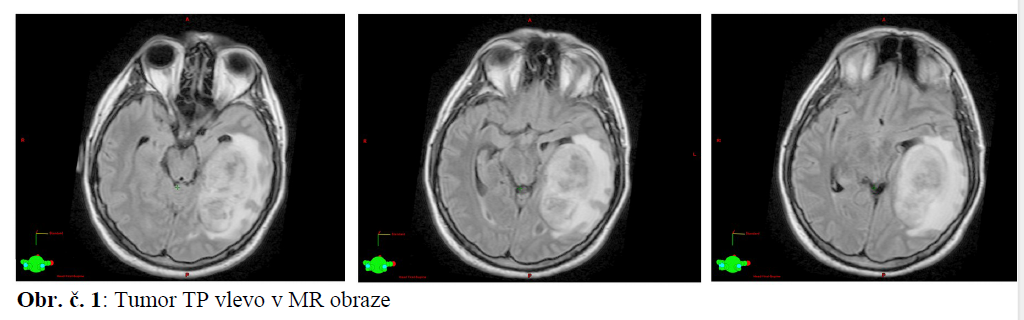

24.9.2010 MR mozku: TP expanzivní proces (cystoidní i solidní), kaudálním okrajem dosahuje až k tentoriu, velikosti 36x68x46mm. V okolí edém, dislokace středu asi o 14 mm do strany pravé.

Pacientovi M.P., v jeho 36 letech, byla stanovena dg Glioblastoma multiforme (GBM) WHO gr. IV. vlevo parietotemporálně.